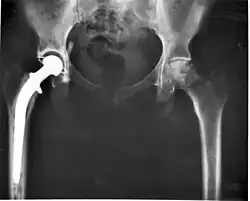

The modern total hip replacement was pioneered by Sir John Charnley, expert in tribology at Wrightington Hospital, in England in the 1960s.[10] He found that joint surfaces could be replaced by implants cemented to the bone. His design consisted of a stainless steel, one-piece femoral stem and head, and a polyethylene acetabular component, both of which were fixed to the bone using PMMA (acrylic) bone cement. For over two decades, the Charnley low-friction arthroplasty and its derivative designs were the most-used systems in the world. This formed the basis for all modern hip implants.

The Exeter hip replacement system (with a slightly different stem geometry) was developed at the same time. Since Charnley, improvements have been continuous in the design and technique of joint replacement (arthroplasty) with many contributors, including W. H. Harris, the son of R. I. Harris, whose team at Harvard pioneered uncemented arthroplasty techniques with the bone bonding directly to the implant.

Arthroplasty is an orthopedic surgery where the articular surface of a musculoskeletal joint is replaced, remodeled, or realigned by osteotomy or some other procedure.[25] It is an elective procedure that is done to relieve pain and restore function to the joint after damage by arthritis (rheumasurgery) or some other type of trauma.[25] As well as the standard total knee replacement surgery, the unicompartmental knee replacement, in which only one weight-bearing surface of an arthritic knee is replaced, may be performed,[25] but it bears a significant risk of revision surgery.[26] Joint replacements are used for other joints, most commonly the hip[27] or shoulder.[28]

A post-surgical concern with joint replacements is wear of the bearing surfaces of components.[29] This can lead to damage to the surrounding bone and contribute to eventual failure of the implant.[29] The plastic chosen is usually ultra-high-molecular-weight polyethylene, which can also be altered in ways that may improve wear characteristics.[29] The risk of revision surgery has also been shown to be associated with surgeon volume.[28][30]